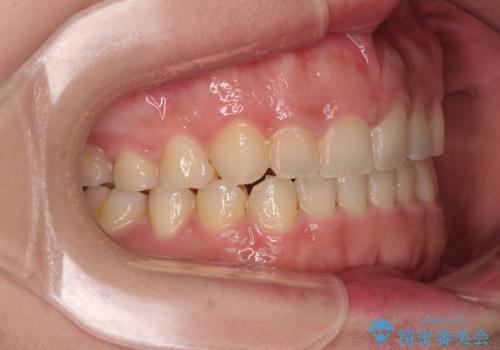

捻れて前に出ている前歯 ワイヤー装置での非抜歯矯正

舌の突出癖がなかなか改善されず、上下前歯が接触するようになるまでに長期間を要しました。

ワイヤー矯正でもインビザラインでも対応可能でしたが、上顎歯列が前方位であるときには、ワイヤー矯正の方がより良い仕上がりとなる可能性が高いため、ワイヤー矯正をおすすめいたしました。